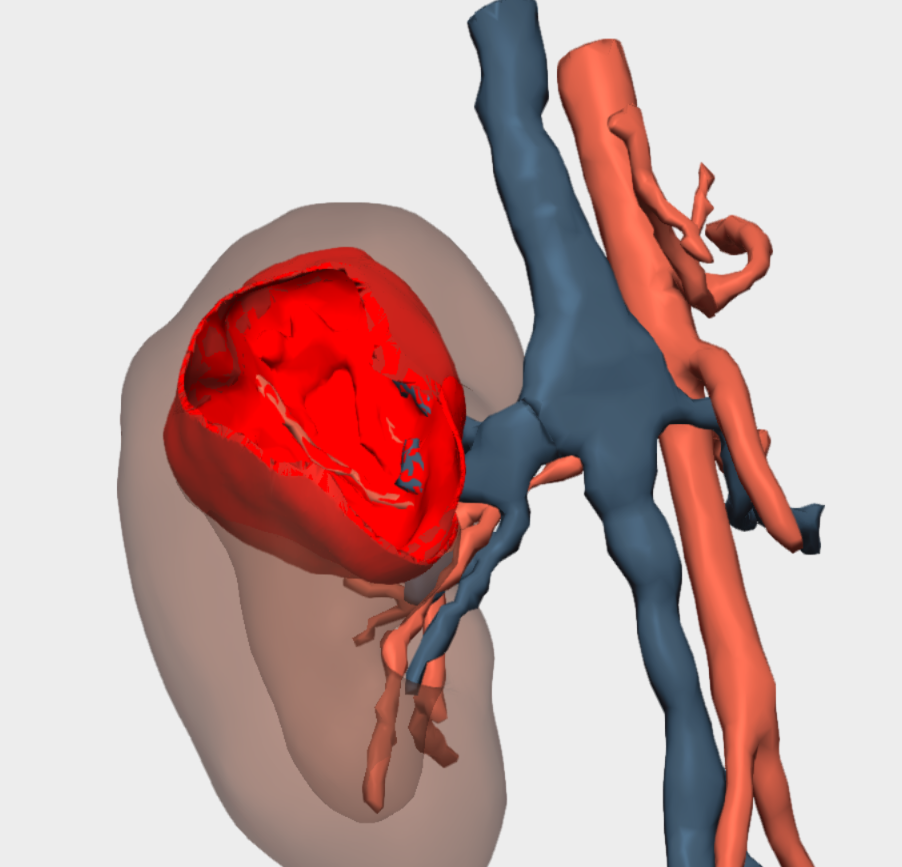

Following multidisciplinary assessment by the Oncology Committee, a right upper pole laparoscopic heminephrectomy was indicated for diagnostic histopathological analysis. Imaging studies were inconclusive and did not allow definitive diagnosis or exclusion of malignancy. Additional imaging performed at the Complejo Hospitalario Universitario de Albacete, including MRI and angio-CT, anticipated significant challenges in vascular localisation and dissection. The renal artery and vein bifurcated within the kidney, beneath the tumour and in close contact with it. Furthermore, the small calibre of these vessels limited precise visualisation of their anatomical course.

Three-dimensional reconstruction enabled precise localisation of the vascular bifurcation, revealing the presence of two arteries and two veins supplying each renal moiety —an anatomically relevant finding that had not been previously identified and was critical for surgical planning.

Detailed 3D anatomical analysis, combined with advanced functionalities such as arterial territory assessment and the ability to work intraoperatively with dual visualisation —3D reconstruction and laparoscopy displayed simultaneously— was a key factor in the success of the procedure.

The surgery was completed successfully following selective vascular control, without clamping of the renal hilum, thereby minimising the risk of injury to the healthy renal moiety. No intraoperative complications were observed.

To sum it up, in this case, 3D reconstruction enabled detailed visualisation of the renal vascular anatomy, facilitating preoperative planning and optimising the surgical strategy. This approach reduced intraoperative morbidity, shortened operative time and, most importantly, preserved the healthy renal moiety.